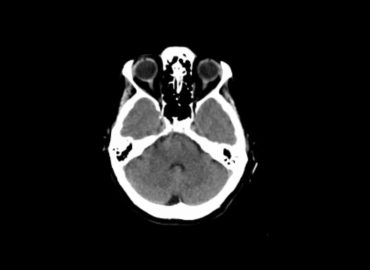

Paciente de 11 años. Alteración de sensorio.